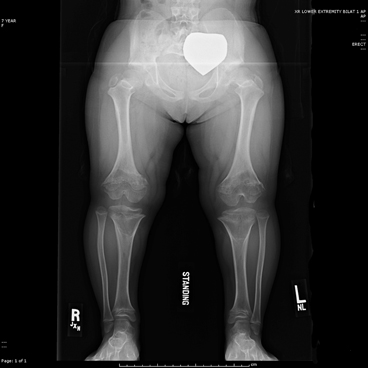

La síndrome de Proteus es una enfermedad genética rara que se caracteriza por el crecimiento excesivo y asimétrico de huesos, piel y otros tejidos del cuerpo. Los síntomas suelen aparecer entre los 6 y 18 meses de edad y el crecimiento desproporcionado se detiene en la adolescencia.

Las principales características y síntomas de la síndrome de Proteus incluyen deformaciones en brazos, piernas, cráneo y médula espinal, asimetría corporal, exceso de pliegues cutáneos, problemas en la columna vertebral, un rostro más alargado, problemas cardíacos, verrugas y manchas claras en el cuerpo, aumento del tamaño del bazo, hipertrofia digital (aumento del diámetro de los dedos) y retraso mental.